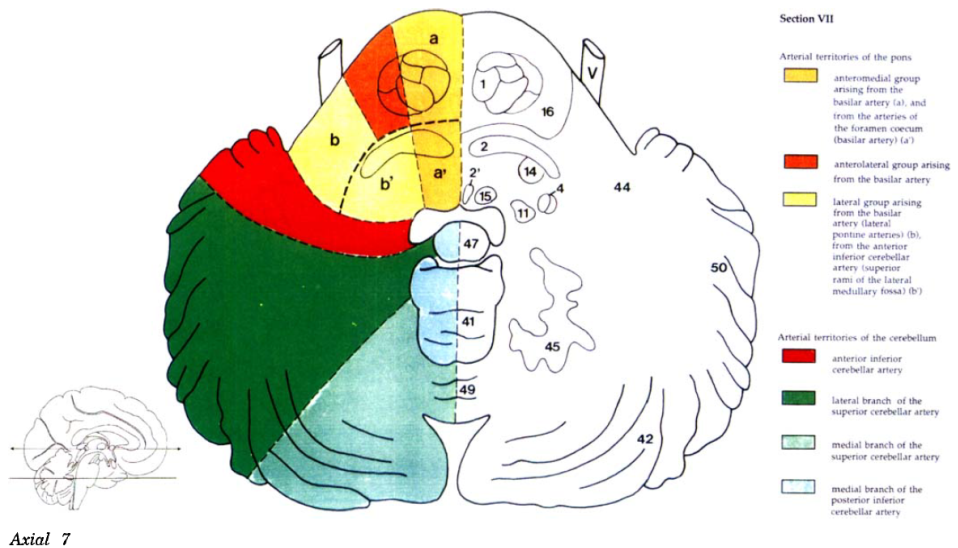

Cerebral vascular territories

Brainstem